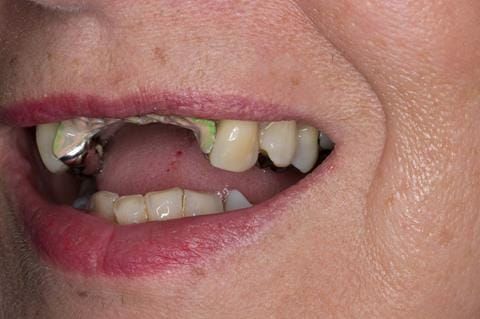

Provision of a maxillary cobalt chromium based partial denture/protective occlusal splint in a heavily restored dentition

- UR2 peri-radicular periodontitis with a peri-radicular area on the root apex. Retrograde amalgam filling from a previous apicectomy. No visible root canal or root canal filling. Large circumferential marginal gap between the crown and tooth. Large post and core present. Very little tooth structure remaining resulting in a fragile tooth with increased potential for fracture.

- UR1 peri-radicular periodontitis with a small peri-radicular area on the root apex with wide blunderbuss apex. Radio-opaque root canal filling present approximately 3 mm short of the radiographic apex. Large circumferential marginal gap between the crown and tooth. Large post and core present. Very little tooth structure remaining resulting in a fragile tooth with increased potential for fracture.

- UL1 peri-radicular periodontitis with a peri-radicular area on the root apex. Retrograde amalgam filling from a previous apicectomy. Visible root canal space with no sign of root canal filling. Large circumferential marginal gap between the crown and tooth. Large post and core present. Very little tooth structure remaining resulting in a fragile tooth with increased potential for fracture.

- UL2 peri-radicular periodontitis with a peri-radicular area on the root apex. No visible root canal or root canal filling. Large circumferential marginal gap between the crown and tooth. Large post and core present. Very little tooth structure remaining resulting in a fragile tooth with increased potential for fracture.

- High smile line showing gum above gingival zeniths of upper front teeth when smiling. Aesthetic failure of the upper four incisors with inflammation of the gingivae and mis-match of the gingival zenith levels.

- Other than the maxillary incisors the remaining dentition was in marginally better condition being moderately to heavily restored. Many will probably require replacement and restoration from time to time mainly from wear and tear owing to occlusal forces.